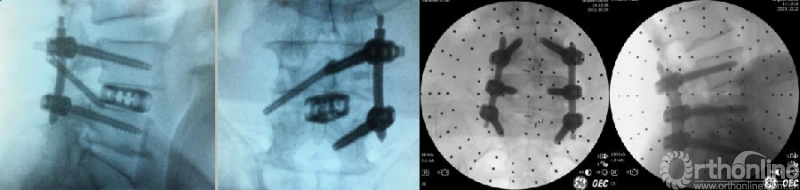

(10)植骨与融合器置入

椎间隙处理完毕后,置换根据减压碎骨量决定是否需要同种异体骨或人工骨。置换舌形工作套管,在内镜直视下逆时针旋转,将套管舌形部分插入到行走根腹侧,并轻轻敲击固定。选择合适大小的试模,C臂正侧位透视下确定确定大小及位置满意。将减压骨块修整成合适大小置入椎间隙,并敲实。再次内镜下探查,植骨块无脱落,神经结构被保护良好,确定舌形工作套管位置满意及稳定后,置入合适大小椎间融合器。透视显示矢状位及冠状位各角位置满意。

(11)经皮椎弓根螺钉内固定

根据手术需要决定采用何种内固定方式及顺序。常规是双侧经皮螺钉置入,也可选择减压侧两枚经皮螺钉+对侧棘突椎板关节突复合体螺钉的3钉设计,均能符合生物力学要求。减压侧两枚经皮螺钉单边固定,或者单枚棘突椎板关节突复合体螺钉,适应证非常窄,选择需慎重。传统方法均是在C臂透视辅助下,置入螺钉,有条件的医院可以借助骨科手术机器人或导航等辅助置钉。放入合适长度固定棒,锁紧螺钉,去除钉尾。个别情况下,需要先放置对侧椎弓根螺钉并撑开椎间隙后暂时固定,再行同侧减压和椎间隙置入。